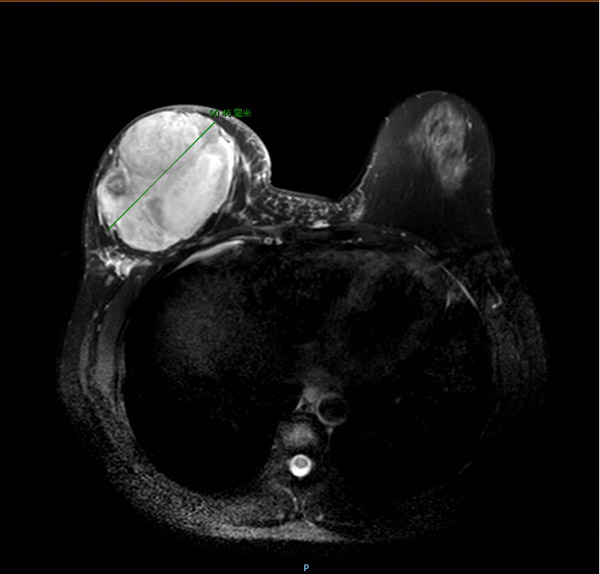

經過完善而系統的檢查,結合病史、查體及輔助檢查,主診醫生覃舒婷副主任醫師考慮譚女士右乳腫瘤為乳腺葉狀腫瘤復發,建議行手術治療。可在這時,原本有著堅定手術意愿的她卻動搖了,因為醫生的建議是右乳乳腺的全部切除!“為什么我的乳房要全部切掉!”不解的譚女士及家屬來到醫生辦公室詢問,覃醫生耐心地為患者解答了疑惑,結合磁共振影像,譚女士明白了,磁共振圖像上,右乳內近10cm的巨大腫瘤,已經將正常腺體組織壓迫到所剩無幾,殘余的腺體不僅不能支撐一個正常的乳房,還可能再次復發。